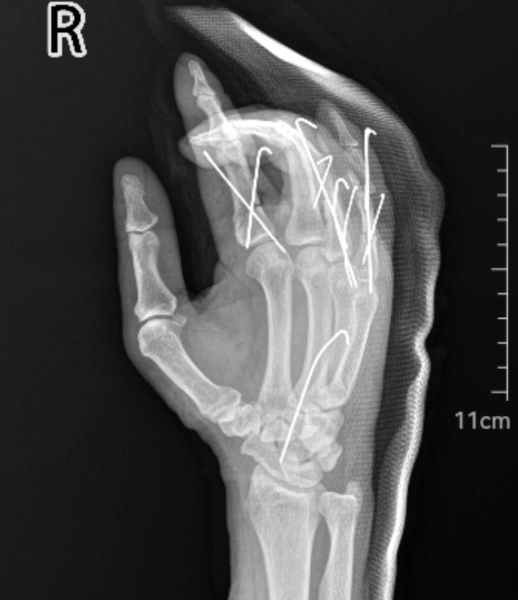

术中,手外科分院一病区医生姜龙、鲁一村共为患者打入克氏针用于固定骨折和关节,修复了多条肌腱和关节囊,并使用比头发丝还细的9-0、10-0无损伤线,吻合了10根血管和4根神经,成功保指。“患者年龄大,而且损伤为多发伤、损毁严重,尤其是皮肤撕脱和手指多段离断,对医生的血管损伤判断能力和吻合技术是极大考验。只有保证血管吻合通畅率,才能为成功保肢创造可能。”姜龙表示。

多发骨折固定、肌腱神经血管修复、环小指撕脱离断再植术后成功保指